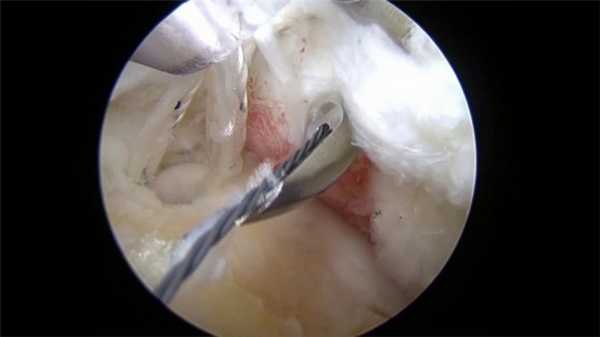

Обычно используется два/три прокола. В один вводится артроскоп, оснащенный источников света и микроскопической видеокамерой, которая передает изображение на монитор. Это позволяет подробно разглядеть все структуры. Одна или два других пункции используются для введения микрохирургических инструментов, необходимых для проведения операции.

Вид изнутри на сустав.

Во время хирургического процесса сначала вводится жидкость, увеличивающая размер сустава. Это позволяет получить более качественное и четкое изображение. Затем делаются проколы (от 1 до 3), в один из которых вводится артроскоп. После постановки диагноза в другие доступы вводятся микроинструменты для проведения операции. В конце операции хирург накладывает швы или пластырные полоски для бесшовного сведения краев ран, закрепляя их мягкой повязкой.